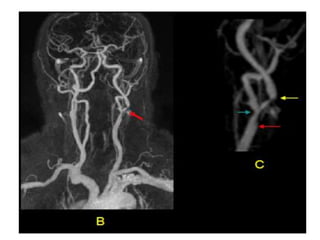

O documento fornece informações sobre como realizar exames de ressonância magnética do pescoço e angiorressonância magnética das carótidas, incluindo parâmetros, programação, anatomia, exames estruturais e funcionais, dicas e protocolos.